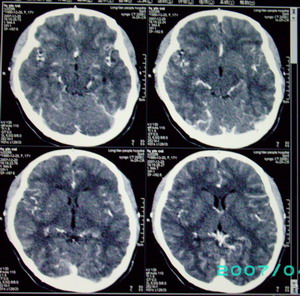

以下是引用九目段在2007-12-24 14:55:00的发言:[br]1,年轻女性[br]2,ct表现:左侧脑室三角区可见一不规则小明显强化的结节,中央见小低密度,侧脑室无扩张。[br]分析:[br]常见的有三种肿瘤好发三角区:[br]1,脉络丛乳头状瘤,好发于年轻者,明显强化,实性,分泌脑脊液,常伴有侧脑室扩大,肿瘤较小可以脑室扩大不明显,不能排除,但小结节尚不易形成坏死腔。[br]2,室管膜瘤,好发于儿童及青少年,明显强化,易坏死,大时伴脑室扩张。[br]3,脑膜瘤,明显强化,圆形,界请,无脑积水,一般不坏死。[br]诊断:[br]左侧脑室三角区结节,考虑室管膜瘤可能性大,不排除脉络丛乳头状瘤和脑膜瘤(因病史较长)。[br][br][本贴已被 九目段 于 2007-12-24 15:13:35 修改过]